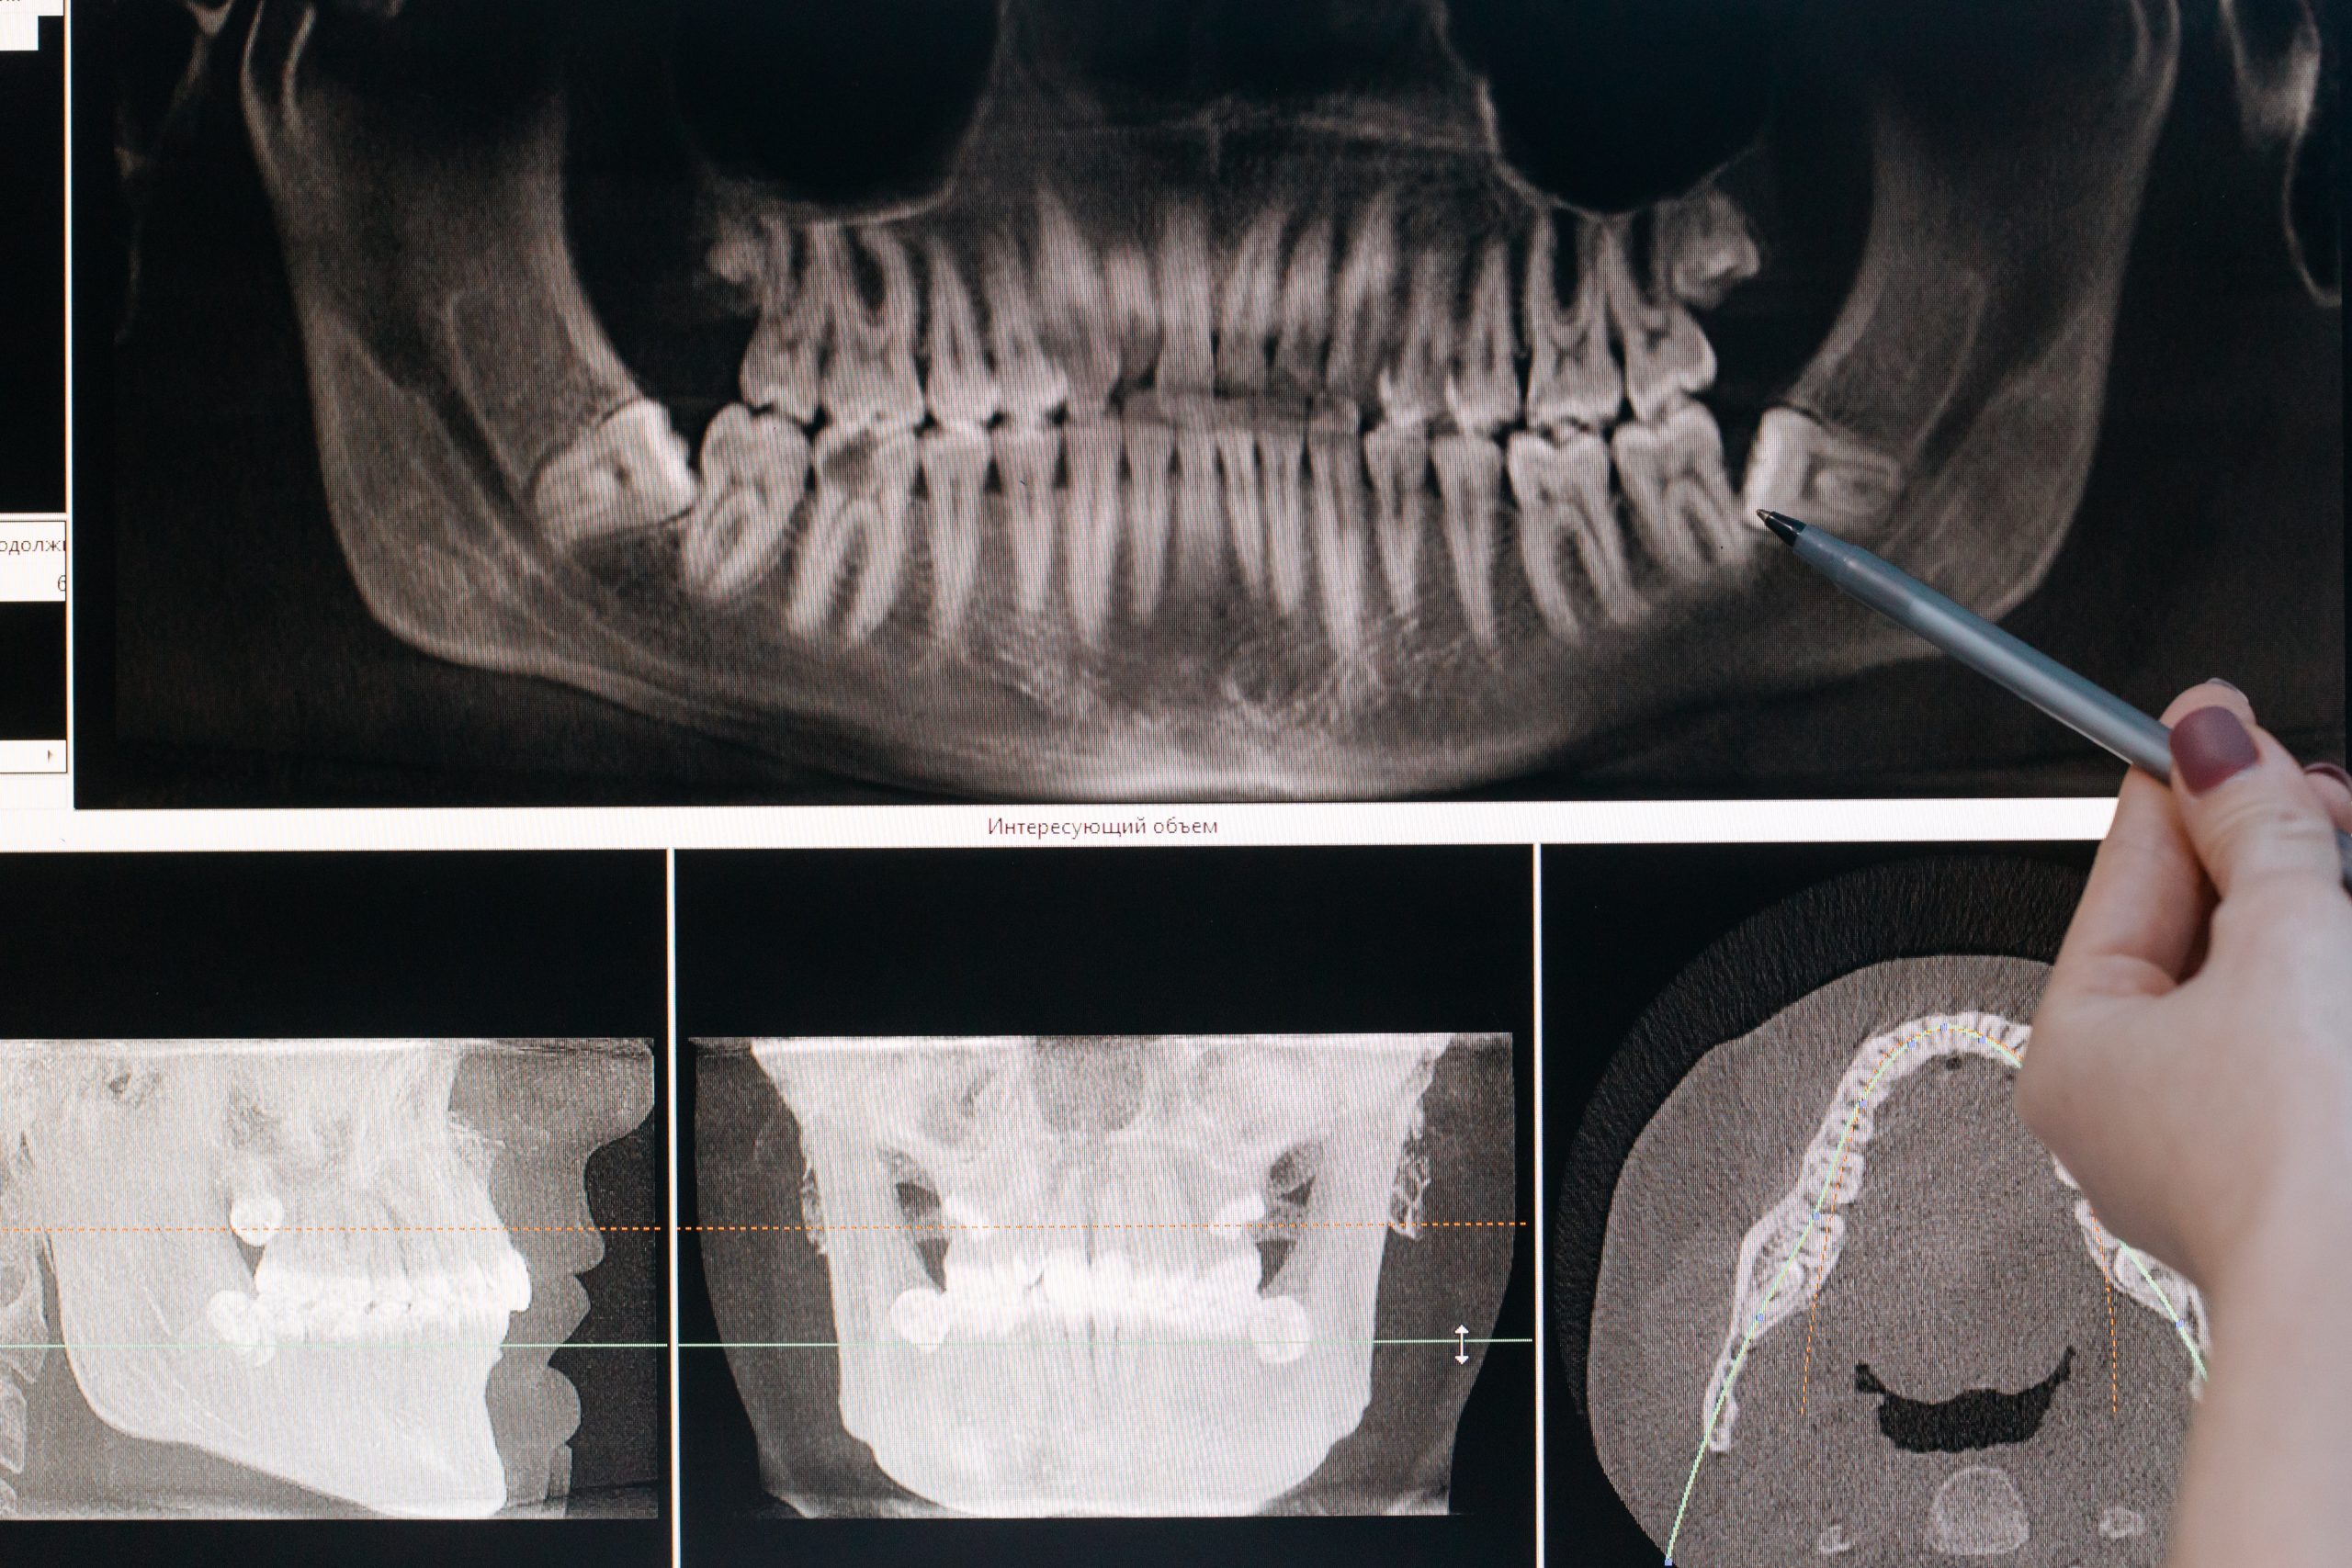

คือการใช้รังสี เอกซเรย์ฟัน เพื่อถ่ายภาพช่องปาก เป็นรังสีชนิดเดียวกับที่ใช้เอกซเรย์ทางการแพทย์อย่างการเอกซเรย์ปอด ทรวงอก หรือช่องท้อง แต่จะใช้ปริมาณรังสีที่น้อยกว่ามาก จึงมีความปลอดภัยสูง และมีความเสี่ยงในการเกิดผลข้างเคียงน้อยมาก ภาพถ่ายที่ได้จากรังสีเอกซ์นั้น จะเป็นภาพสีขาว – ดำที่มีความเข้มของสีแตกต่างกัน ขึ้นอยู่กับการดูดซับของรังสี โดยจะเห็นกระดูกเป็นสีขาว ในขณะที่ไขมันและเนื้อเยื่ออื่น ๆ ที่ดูดซับรังสีได้น้อยจะเห็นเป็นสีเทา จึงทำให้ทันตแพทย์สามารถตรวจดูสภาพฟันและกระดูกเบ้าฟันได้อย่างละเอียด ช่วยให้สามารถประเมินความเสี่ยงในการเกิดฟันผุ หรือปัญหาฟันต่าง ๆ อาจเกิดขึ้นได้ และวางแผนการรักษาได้อย่างเหมาะสมนั่นเอง

จุดประสงค์หลักของการถ่ายภาพเอกซเรย์ช่องปากและฟันของคนไข้นั้น ทันตแพทย์จะใช้เป็นแหล่งข้อมูลสำคัญที่ใช้ในการวินิจฉัยโรค และวางแผนรักษาทางทันตกรรมต่าง ๆ ไม่ว่าจะเป็น ถอนฟัน ดูรอยฟันผุ จัดฟัน รักษาโรคเหงือก หรือตรวจหาฟันคุด ไปจนถึงตรวจติดตามผลการรักษา

เพื่อให้คุณมองเห็นภาพประโยชน์ของการเอกซเรย์ช่องปากและฟันได้ชัดเจนมากยิ่งขึ้น เราได้รวมเคสตัวอย่างเกี่ยวกับการเอกซเรย์ฟันมาให้แล้ว จะน่าสนใจแค่ไหนนั้น ไปดูกันเลย

เป็นหนึ่งในเคสที่พบบ่อยที่สุด โดยการถ่ายภาพเอกซเรย์จะช่วยให้ทันตแพทย์ศึกษารายละเอียดของฟันที่จะถอน หรือผ่าฟันคุดออกได้ดีขึ้น ไม่ว่าจะเป็น ความโค้งงอของรากฟัน ขนาดของรอยผุที่ส่งผลให้ฟันแตกได้ง่ายขณะถอนฟัน หรือลักษณะและตำแหน่งของฟันคุดว่าอยู่ใกล้กับบริเวณที่ควรระมัดระวังอย่างเส้นประสาทของขากรรไกรล่างไหม  ซึ่งจะช่วยให้การถอนฟันเป็นไปอย่างปลอดภัยมากยิ่งขึ้น

การถ่ายภาพเอกซเรย์จะช่วยให้ทันตแพทย์ตรวจดูระดับความรุนแรงของโรคเหงือกอักเสบ และตรวจดูลักษณะการถูกทำลายของกระดูกที่หุ้มรากฟัน เพื่อวางแผนการรักษาอย่างเหมาะสมได้ โดยในระยะแรกจะยังไม่เห็นการเปลี่ยนแปลงในภาพรังสี แต่ถ้าโรคลุกลามมาก ๆ จนเกิดการอักเสบ จะตรวจพบร่องลึกปริทันต์ และการละลายของกระดูกที่ห้อมรอบรากฟันอยู่ได้นั่นเอง

ไม่ว่าคุณจะจัดฟันใส Invisalign หรือจัดฟันแบบโลหะ จะต้องทำการเอกซเรย์ช่องปากและฟันเป็นขั้นตอนแรกก่อนเสมอ เพื่อที่ทันตแพทย์จะได้ตรวจดูลักษณะของฟัน กระดูกขากรรไกร กะโหลกศีรษะและใบหน้าโดยละเอียด และวางแผนการรักษาได้อย่างแม่นยำและมีประสิทธิภาพมากที่สุด ซึ่งในบางคนที่เอกซเรย์แล้วเจอฟันคุด ก็จำเป็นที่จะต้องผ่าฟันคุดออกให้เรียบร้อยด้วย